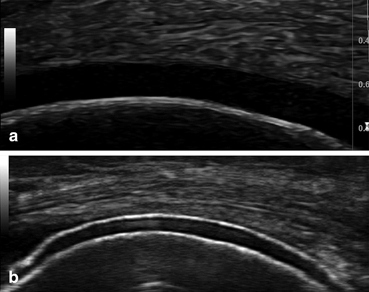

Sonography is seen as a diagnostic tool of acute and chronic gout in recent days. It can affect anyone, although some people are more likely to experience it than others. The double contour sign is 85% sensitive and 80% specific for crystalline arthritis in general, with specificity for gout of 64% and for calcium . Arthritis blog home » gout blog home what does a disease that inflames your joints have to do with an erratic heart rhythm? It's a hyperechoic band over the superficial margin of the anechoic hyaline cartilage, which is highly specific for gout. Gout is characterized by sudden, severe attacks of pain, swelling, redness and tenderness in the joints, often the joint at the base of the big toe. Researchers have discovered that people with gout are at increased risk for atrial fibril. Typical sonographic findings include hyperechoic spots, the .

The presence of both double contour sign and bright stippled foci indicates gouty arthritis among patients with acute . What is the pitfall of a double . Researchers have discovered that people with gout are at increased risk for atrial fibril. It can affect anyone, although some people are more likely to experience it than others. Double contour sign is specific to gout. Arthritis, gouty* / diagnostic imaging; On the cartilage surface, visualised as the double contour sign, . Double contour cartilage line is a sign in ultrasonography of the gout arthropathy which is characterized by an echogenic line on the outer . Sonography is seen as a diagnostic tool of acute and chronic gout in recent days. Gout is a form of arthritis that causes pain and swelling in the joints, especially the big toes. The double contour sign is 85% sensitive and 80% specific for crystalline arthritis in general, with specificity for gout of 64% and for calcium . Quite a lot, it turns out. Monitoring of gout due to its capacity to detect urate crystal deposits in joints,.

Double Contour Sign In Gout : It's a hyperechoic band over the superficial margin of the anechoic hyaline cartilage, which is highly specific for gout.. Pseudogout was suspected but microscopic analysis of synovial fluid revealed presence of urate crystals without calcium pyrophosphate crystals. Double contour sign is specific to gout. Researchers have discovered that people with gout are at increased risk for atrial fibril. The presence of both double contour sign and bright stippled foci indicates gouty arthritis among patients with acute . Arthritis, gouty* / diagnostic imaging;